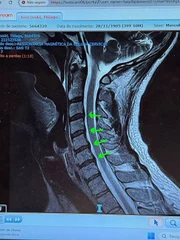

Tiago Iorc mostrou os exames que fez na unidade de saúde

Instagram/Reprodução

Tiago Iorc revela detalhes do procedimento para tratar hérnia

Diagnóstico

Ainda na publicação, o cantor detalhou seu quadro: “De forma bem simplificada, entre cada uma de nossas vértebras existem discos que funcionam como ‘amortecedores’. Esse amortecimento é o que tira o atrito direto de uma vértebra com a outra. Diferentes causas podem causar com que esses discos sejam esmagados pelas vértebras e isso faz com que elas causem um herniamento, uma protrusão. Esse volume extra acaba invadindo o espaço de nervos que passam e se ramificam a partir da coluna, e é esse esmagamento que causa dor, além de outros sintomas”, relatou.